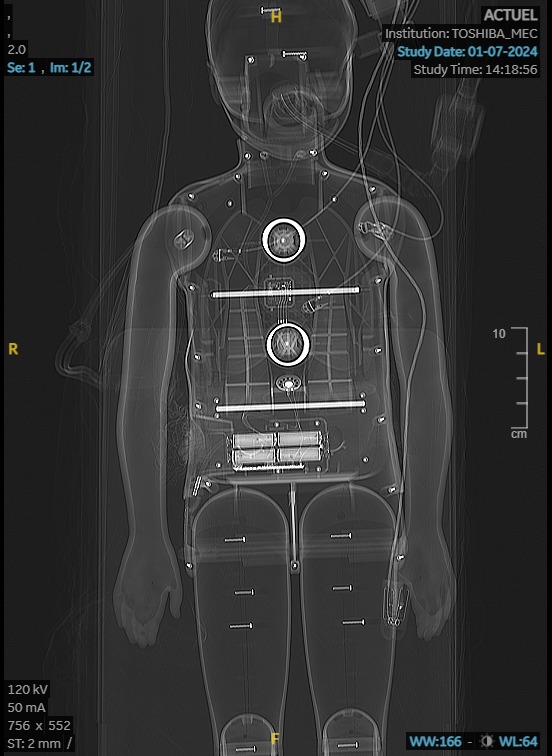

Simulation AMAVI in situ

Le 1er juillet 2024

au pôle de pédiatrie de l'hôpital de Hautepierre

qui organisait un exercice d'afflux massif d'enfants blessés.

La simulation portait sur la survenue d'une explosion dans un établissement scolaire.